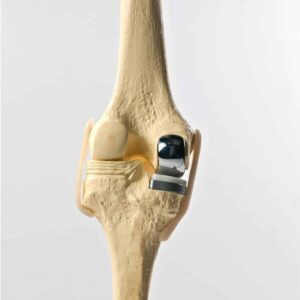

Partial knee replacement (PKR), also known as unicondylar or unicompartmental knee replacement, is a surgical procedure that replaces only the damaged portion of the knee joint, while preserving the healthy parts. Unlike total knee replacement, PKR focuses on restoring function by targeting one or two specific compartments of the knee.